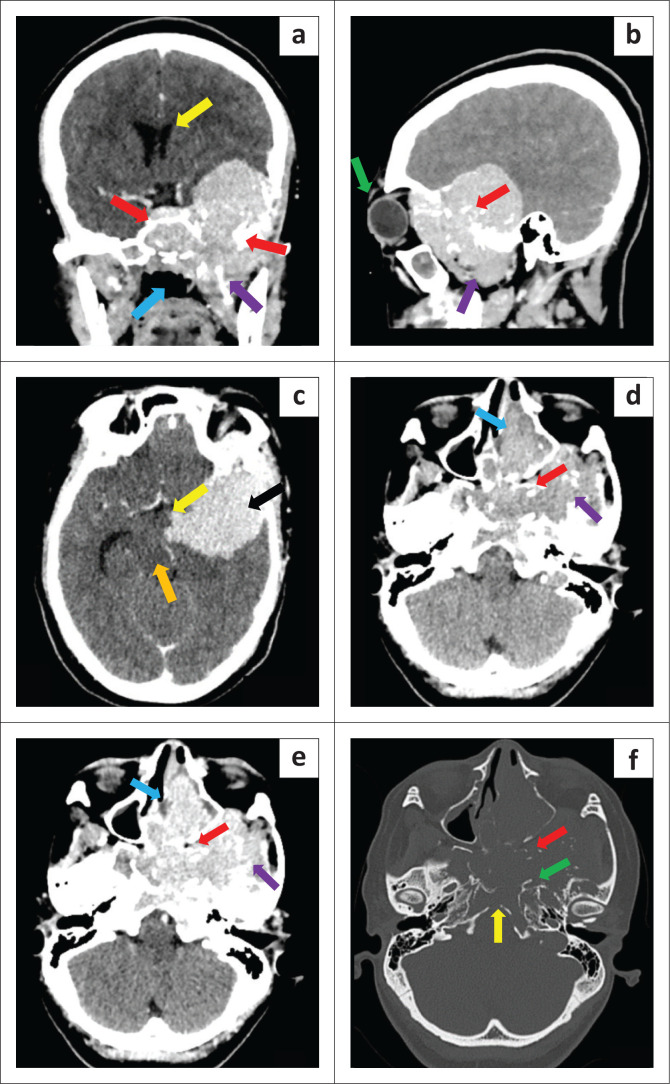

Plasma cell neoplasia has a wide presentation of disease (localised or systemic) according to the International Myeloma Working Group. Radiological imaging identifies plasmacytomas as solitary lesions or part of multiple myeloma. We present a rare case of a 21-year-old female who presented with a skull-base tumour.

Contribution: A head and neck plasmacytoma with further lytic bone lesions was confirmed on imaging. This article presents and discusses the clinical, CT, MRI, positron emission tomography (PET)-CT, histology and laboratory findings.